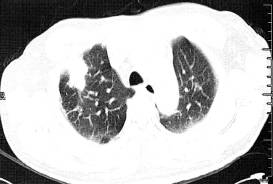

(2)肺转移瘤结节边缘光整,部分病灶融合,出现分叶征。常难与肺癌鉴别,其转移 瘤可能性与原发肿瘤组织类型和患者年龄密切相关,常见原发肿瘤包括黑色素瘤、肉瘤、结肠癌、乳腺癌、肝癌、肾癌、膀胱癌和睾丸癌等(图3)。诊断主要依靠原发恶性肿瘤病史。 医学百科网 | YxBaike.Com